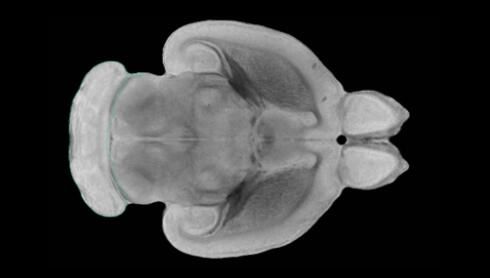

近日,一項刊登在國際雜志Nature上的研究報告中,來自劍橋大學(xué)的科學(xué)家們通過研究揭示了隨著年齡增長大腦僵硬程度的增加導(dǎo)致大腦干細(xì)胞功能異常的分子機(jī)制,同時研究者還開發(fā)出了一種新方法能將老化的干細(xì)胞逆轉(zhuǎn)回年齡健康狀態(tài);相關(guān)研究結(jié)果有望幫助研究人員理解機(jī)體大腦的老化過程以及如何開發(fā)治療年齡相關(guān)大腦疾病的新型療法。

隨著機(jī)體年齡增加,肌肉和關(guān)節(jié)都會變得僵硬,這就會使得日?;顒幼兊酶永щy,本文研究表明,我們的大腦也是如此,與年齡相關(guān)的大腦僵硬對大腦干細(xì)胞的功能或許有著重要影響。文章中,研究人員對年輕和老化大鼠的大腦進(jìn)行研究闡明了年齡相關(guān)大腦僵硬對少突膠質(zhì)前體細(xì)胞(OPCs,oligodendrocyte progenitor cells)功能的影響。OPCs是一類對維持正常大腦功能非常重要的大腦干細(xì)胞,其對于髓磷脂的再生也非常重要,髓磷脂是神經(jīng)組織周圍的脂肪鞘,在多發(fā)性硬化癥中髓磷脂的再生常常會被損傷,機(jī)體老化對這些細(xì)胞的影響常常會誘發(fā)多發(fā)性硬化癥的發(fā)生,這些細(xì)胞的功能在老化的健康人群中同樣會下降。

為了確定老化OPCs的功能缺失是否可以被逆轉(zhuǎn),研究人員將來自老化大鼠機(jī)體的老化OPCs轉(zhuǎn)移到了年輕大鼠柔軟的海綿狀大腦組織中去,值得注意的是,這些老化的大腦細(xì)胞能夠重新恢復(fù)活力,其行為非常像年輕更加強(qiáng)壯的細(xì)胞。這項研究中,研究人員在實驗室中開發(fā)出了具有可變僵硬程度的新型材料,并在受控環(huán)境下研究這些材料的生長及其對大鼠大腦干細(xì)胞的影響,這些材料能被工程化改造具有和年齡或老化大腦相似的柔軟程度。

為了深入理解大腦組織柔軟和僵硬影響細(xì)胞行為的分子機(jī)制,研究人員對細(xì)胞表面一種名為Piezo1的蛋白質(zhì)進(jìn)行了分析,該蛋白質(zhì)能“告知”細(xì)胞其周圍的環(huán)境為柔軟或僵硬。研究者Kevin Chalut說道,我們發(fā)現(xiàn),當(dāng)在僵硬材料上促進(jìn)年輕具有功能性的大鼠干細(xì)胞時,這些細(xì)胞就會表現(xiàn)出功能異常,并失去其再生的能力,實際上其行為與老化細(xì)胞相似。當(dāng)將老化的大腦細(xì)胞在柔軟材料上生長時,其功能就會表現(xiàn)得像年輕細(xì)胞一樣,換句話說,其能夠重新恢復(fù)年輕的活力。

當(dāng)研究者從老化大腦干細(xì)胞的表面剔除Piezo1蛋白后,他們就能夠誘騙細(xì)胞感知柔軟的周圍環(huán)境,甚至當(dāng)將細(xì)胞在僵硬材料上生長時也是如此。此外,當(dāng)在老化大鼠大腦中剔除OPCs上的Piezo1時,就會促進(jìn)細(xì)胞變得年輕并再次承擔(dān)正常的再生功能。研究者Susan Kohlhaas表示,多發(fā)性硬化癥是一種痛苦讓患者致殘的疾病,隨著時間推移,我們迫切需要開發(fā)出減緩并抑制患者殘疾的新型療法。這項研究中,研究人員闡明了大腦干細(xì)胞老化的分子機(jī)制,以及如何通過逆轉(zhuǎn)該過程來實現(xiàn)恢復(fù)大腦干細(xì)胞活力,后期研究人員將會基于本文研究開發(fā)出新型療法來治療多種與老化和多發(fā)性硬化癥相關(guān)的疾病,包括如何潛在恢復(fù)大腦失去的功能等。